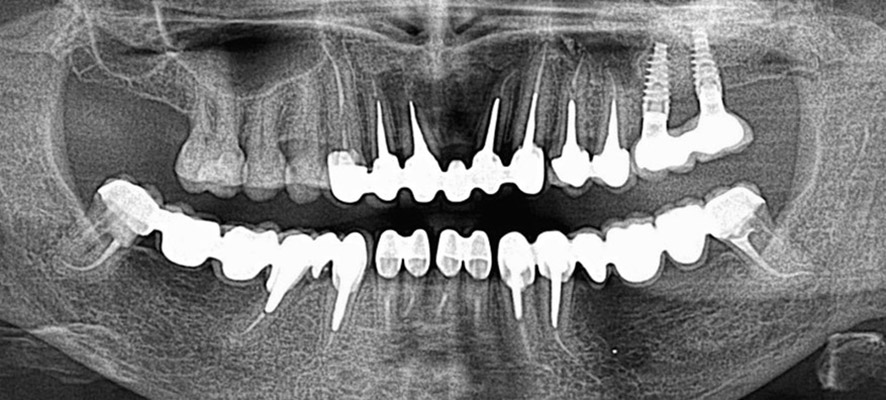

As part of endodontic therapy, we treat root canals using a combination of manual and machine techniques according to the latest research, while the quality of our work is incomparably enhanced by the use of a microscope. By investing in high-quality devices and instruments, we guarantee high success rates of endodontic treatment.

We perform post-endodontic therapy according to indication by reinforcing the endodontically treated tooth with a glass fiber post (fiber post) or a laboratory-made metal post.

Root canal treatment (also called endodontics) is necessary when the blood and nerve supply of the tooth (known as the pulp) is infected by decay or injury. You may not feel pain in the early stages of infection.

In some cases where the tooth darkens, we can conclude that the tooth nerve has died (or is dying). In this situation, root canal treatment is necessary. If the dental pulp becomes infected, the infection can spread through the root canal system of the tooth to the surrounding bone and eventually lead to an abscess.

An abscess is an inflamed area where pus collects, causing later swelling of the tissues around the tooth. Abscess symptoms can range from a dull ache to severe pain, and the tooth may be sensitive when biting.

If root canal treatment is not performed, the infection will spread and extraction will be required. Root canal treatment, or endodontics, cleans the infected pulp chamber and treats the damage. In this way, it is possible to save the tooth.